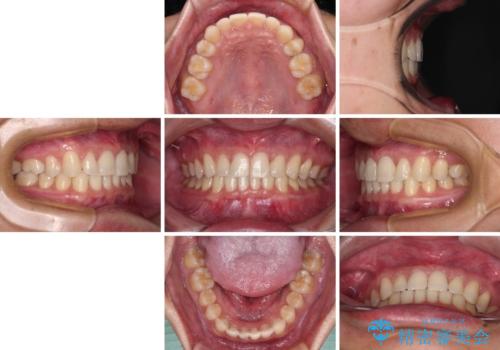

著しいディープバイトと隙間だらけの歯列

- 歯のデコボコと歯の隙間を気にして来院された患者様です。

隙間の原因は、埋伏や前後に重なってしまっている上顎小臼歯と、下の前歯が見えなくなるくらいのディープバイトで、それらを改善する必要がありました。

顕著なディープバイトのため、頻繁に装置が脱離することがあり、治療期間が想定よりも長くかかることがありますが、当初の予定期間で無事に治療を終えることができました。